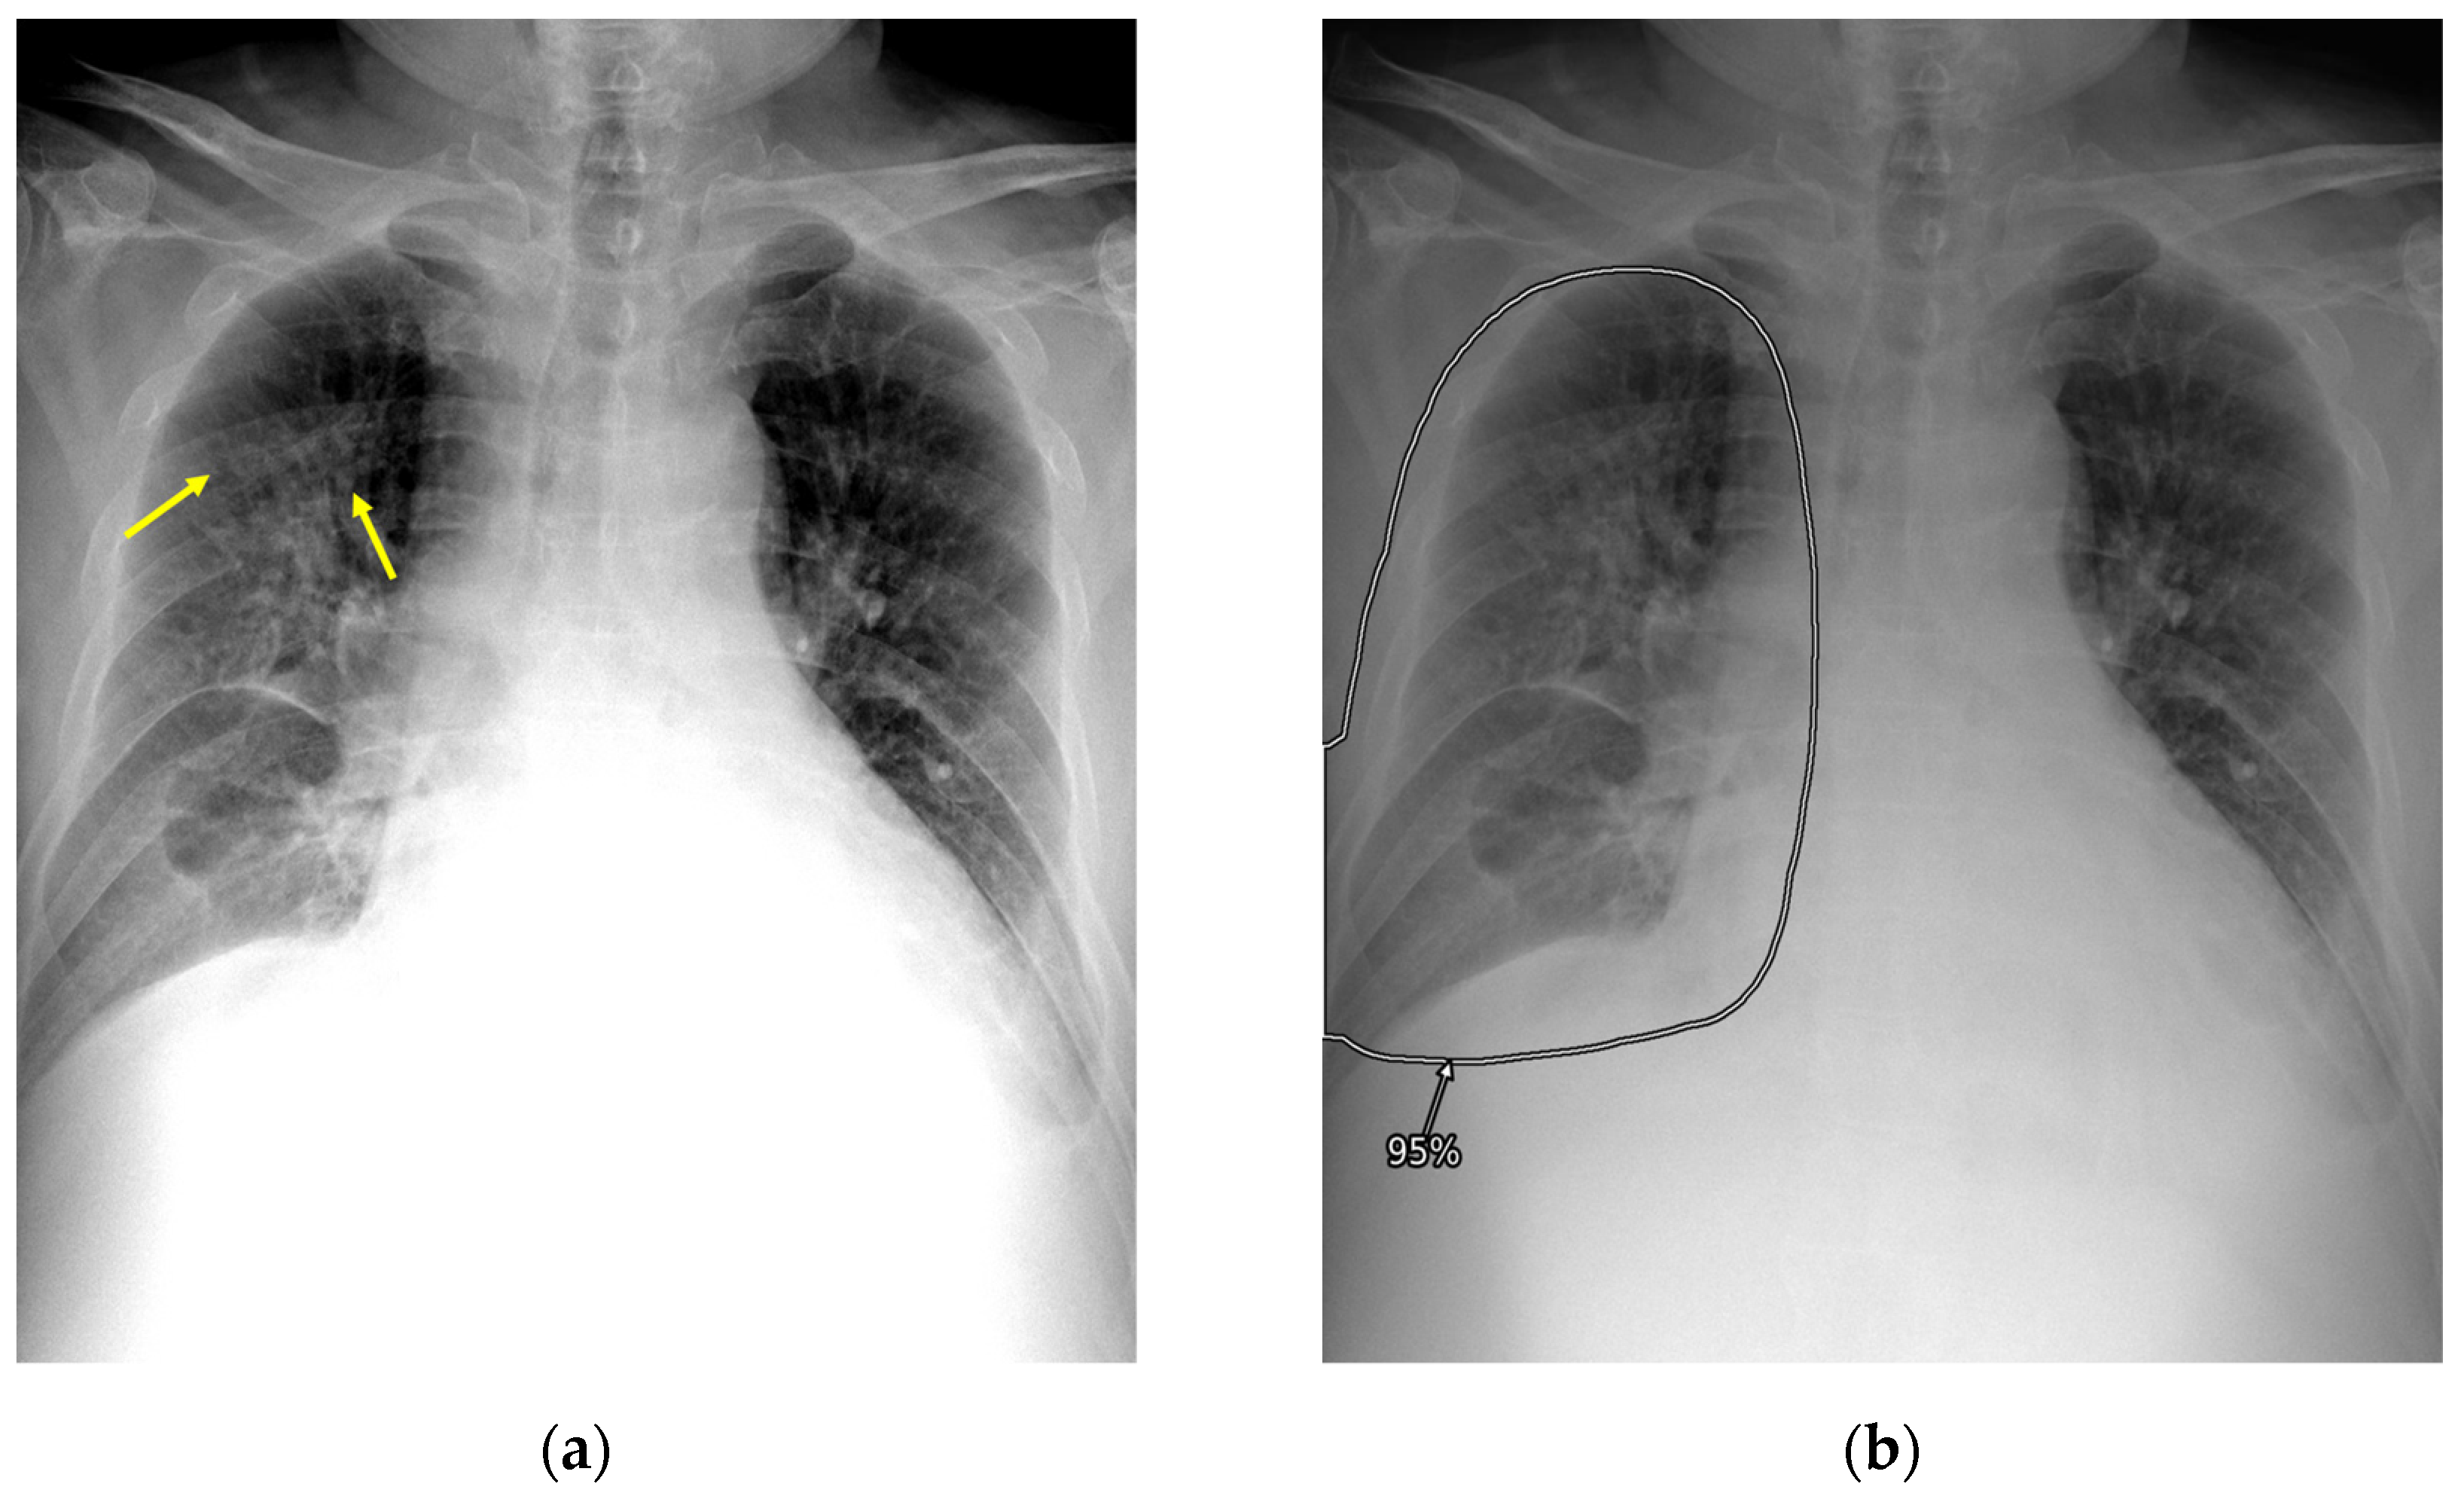

2.3. AI-CAD

2.4. Reader Test